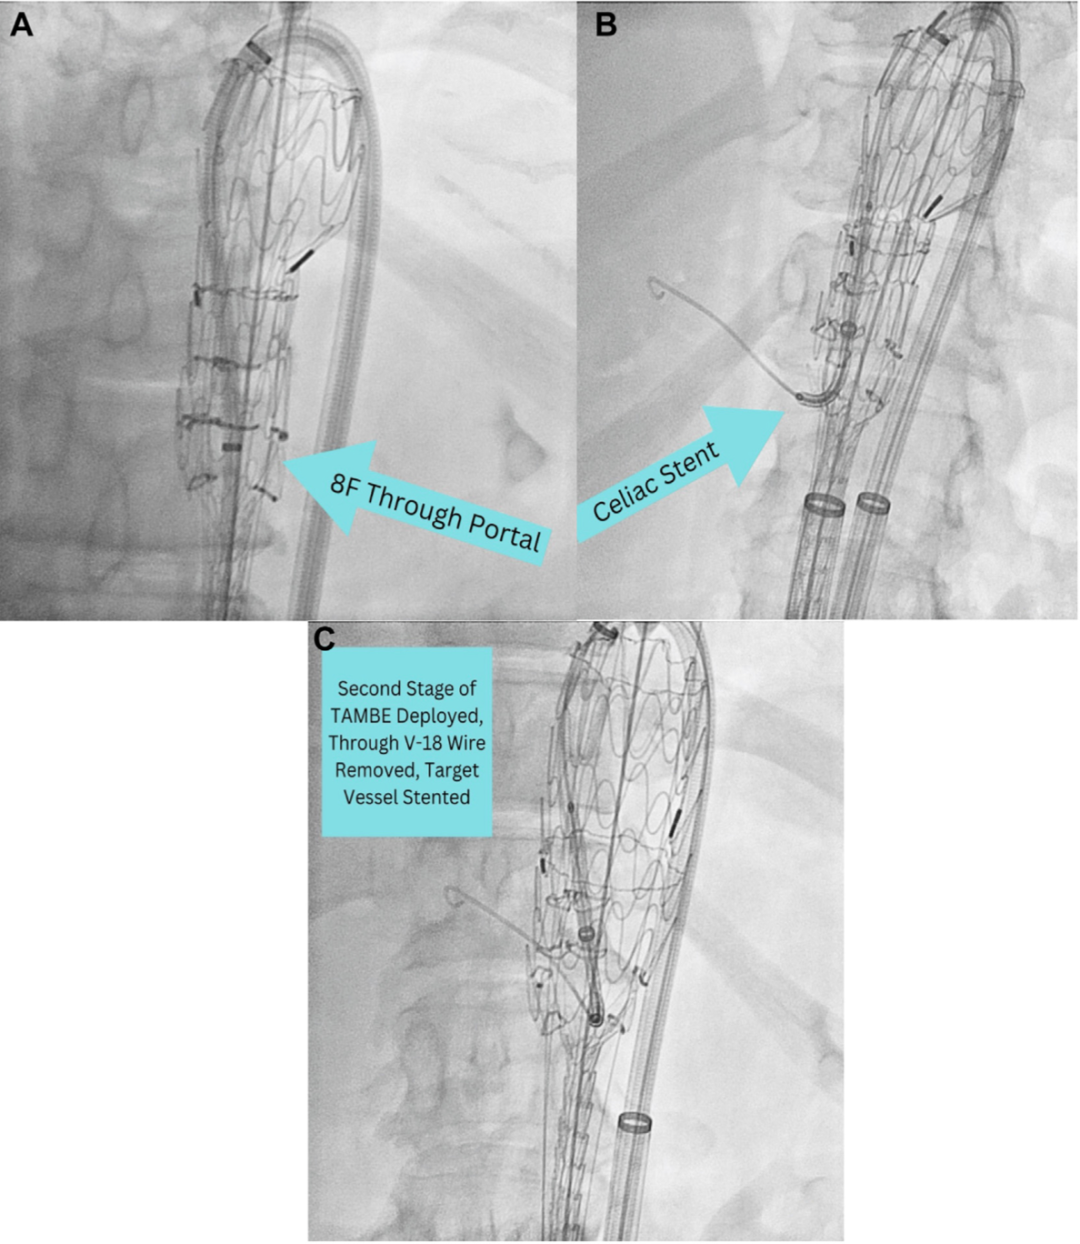

手术步骤示意图:包括放置预置贯穿导丝(A);将装置定位于腹腔干和肠系膜上动脉上方设置顺行分支口、肾动脉下方设置逆行分支口的位置(B);部分释放装置(C);以及使用圈套器将导丝重新引向左股动脉入路点(D)。

释放前准备:将V-18导丝通过可移除导丝管反向穿入后,将其穿过一个可撕裂鞘管圈套器,并插入左股动脉内的22 Fr鞘管中。

装置放置与建立贯穿导丝:胸腹分支腔内移植物(TAMBE)通过其分支口装载了四根V-18导丝,经由左股动脉入路沿一根硬导丝被推送至主动脉内(A)。将8 Fr鞘管置入16 Fr可调弯鞘管内,通过右股动脉入路将其放置在TAMBE装置旁,然后进行TAMBE的第一阶段释放(B)。通过8 Fr鞘管内的圈套器,捕获预先穿过腹腔干分支口的V-18导丝(C)。将V-18导丝拉出8 Fr鞘管,从而建立一根贯穿导丝(D)。